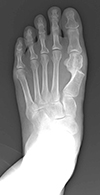

外反母趾

外反母趾とは、足の親指(母趾)が、第2趾の方へ曲がって変形している足の変形です。

母趾の付け根の内側の痛みを生じる場合が多く、バニオンと呼ばれる胼胝(たこ)を形成することもあります。親指の症状だけでなく、第2趾や第3趾の足底痛や足の甲の痛みを生じることもあります。

靴の調整や足底挿板による治療が基本となりますが、変形の矯正のためには母趾の中足骨を骨切りする手術が必要になる場合があります。

外反母趾の手術法は100種類以上あるといわれていますが、当院では患者さんへの侵襲の少ないDLMO(デルモ)法という第1中足骨遠位骨切り術を行っています。この術式は約2cmの皮膚切開で、第1中足骨を骨頭基部で骨切りしたのち、骨片間を鋼線1本で止めるというシンプルな術式です。鋼線は手術後1か月で抜去するので、術後に体の中にインプラント(金属)が残らないこともこの術式の特徴といえます。